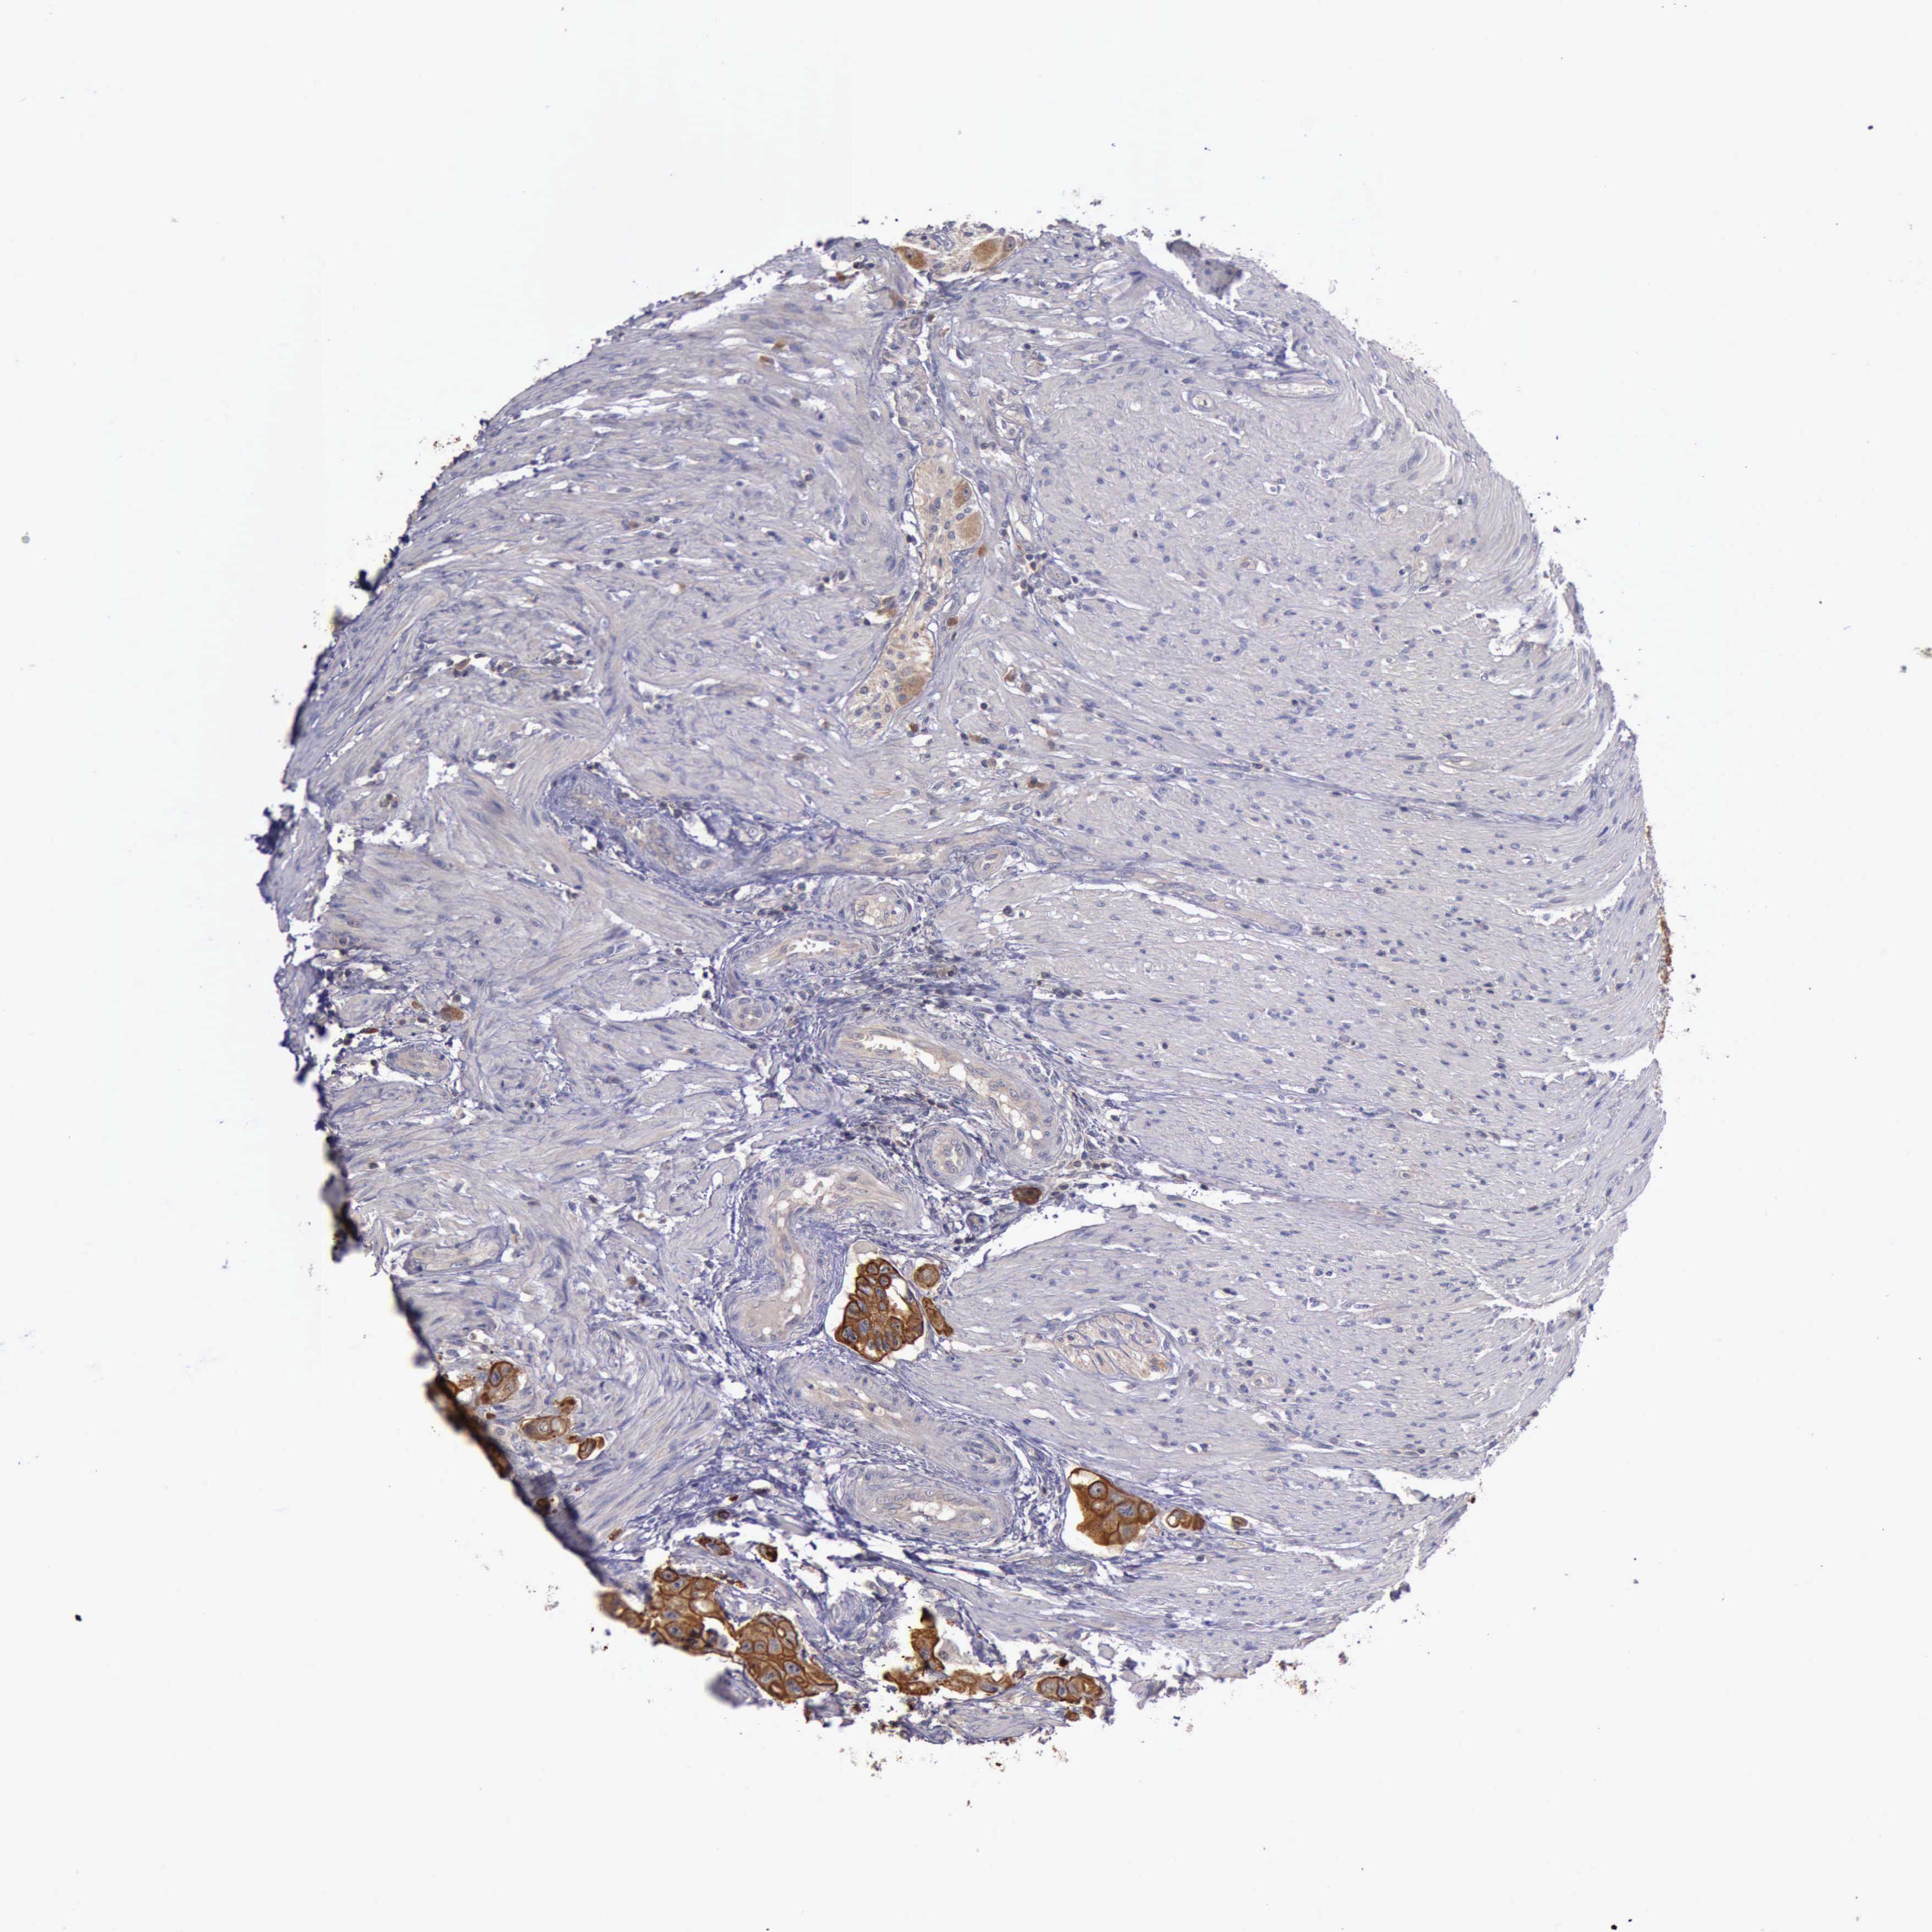

CANCER COLORECTAL CANCER Show tissue menu

Colorectal cancer

Human cancer